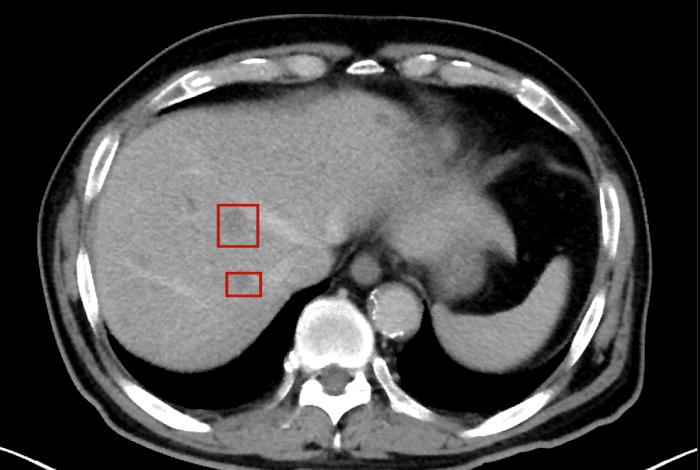

術(shù)后,萬秀萍為黃先生做進一步的檢查,腹部磁共振(MRI)檢查顯示:肝臟區(qū)域出現(xiàn)了轉(zhuǎn)移病灶的陰影。

轉(zhuǎn)移病灶的陰影

3..全程守護:定期進行影像學(xué)復(fù)查(MRI/CT),必要時內(nèi)鏡評估,動態(tài)調(diào)整治療方案。

目前,黃先生的腫瘤活動已得到有效抑制,肝臟轉(zhuǎn)移灶未見爆發(fā)性進展,病情整體保持穩(wěn)定。